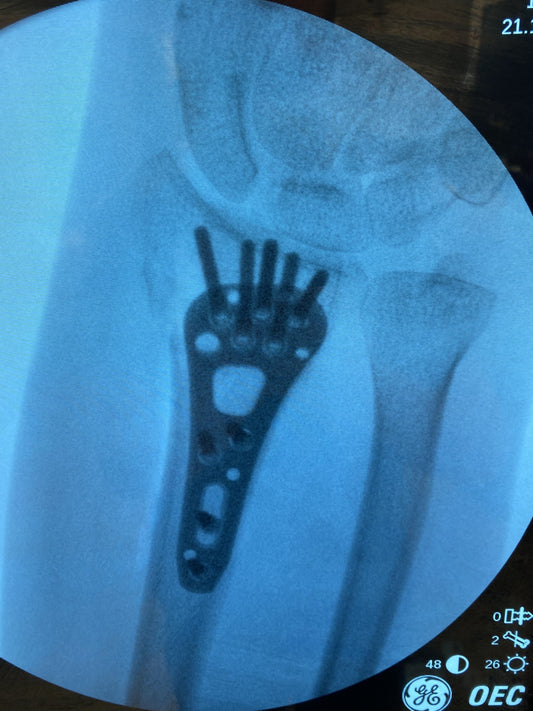

How is a distal radius fracture fixed?

Surgery to correct a distal radius fracture is usually done as a daycase operation under either general anaesthetic (with you asleep) or regional anaesthetic (with you awake or under sedation,...

Does a broken wrist need an operation?

Generally when people talk about a broken wrist they mean the end of the radius bone closest to the hand. This is one of the most commonly broken bones in...